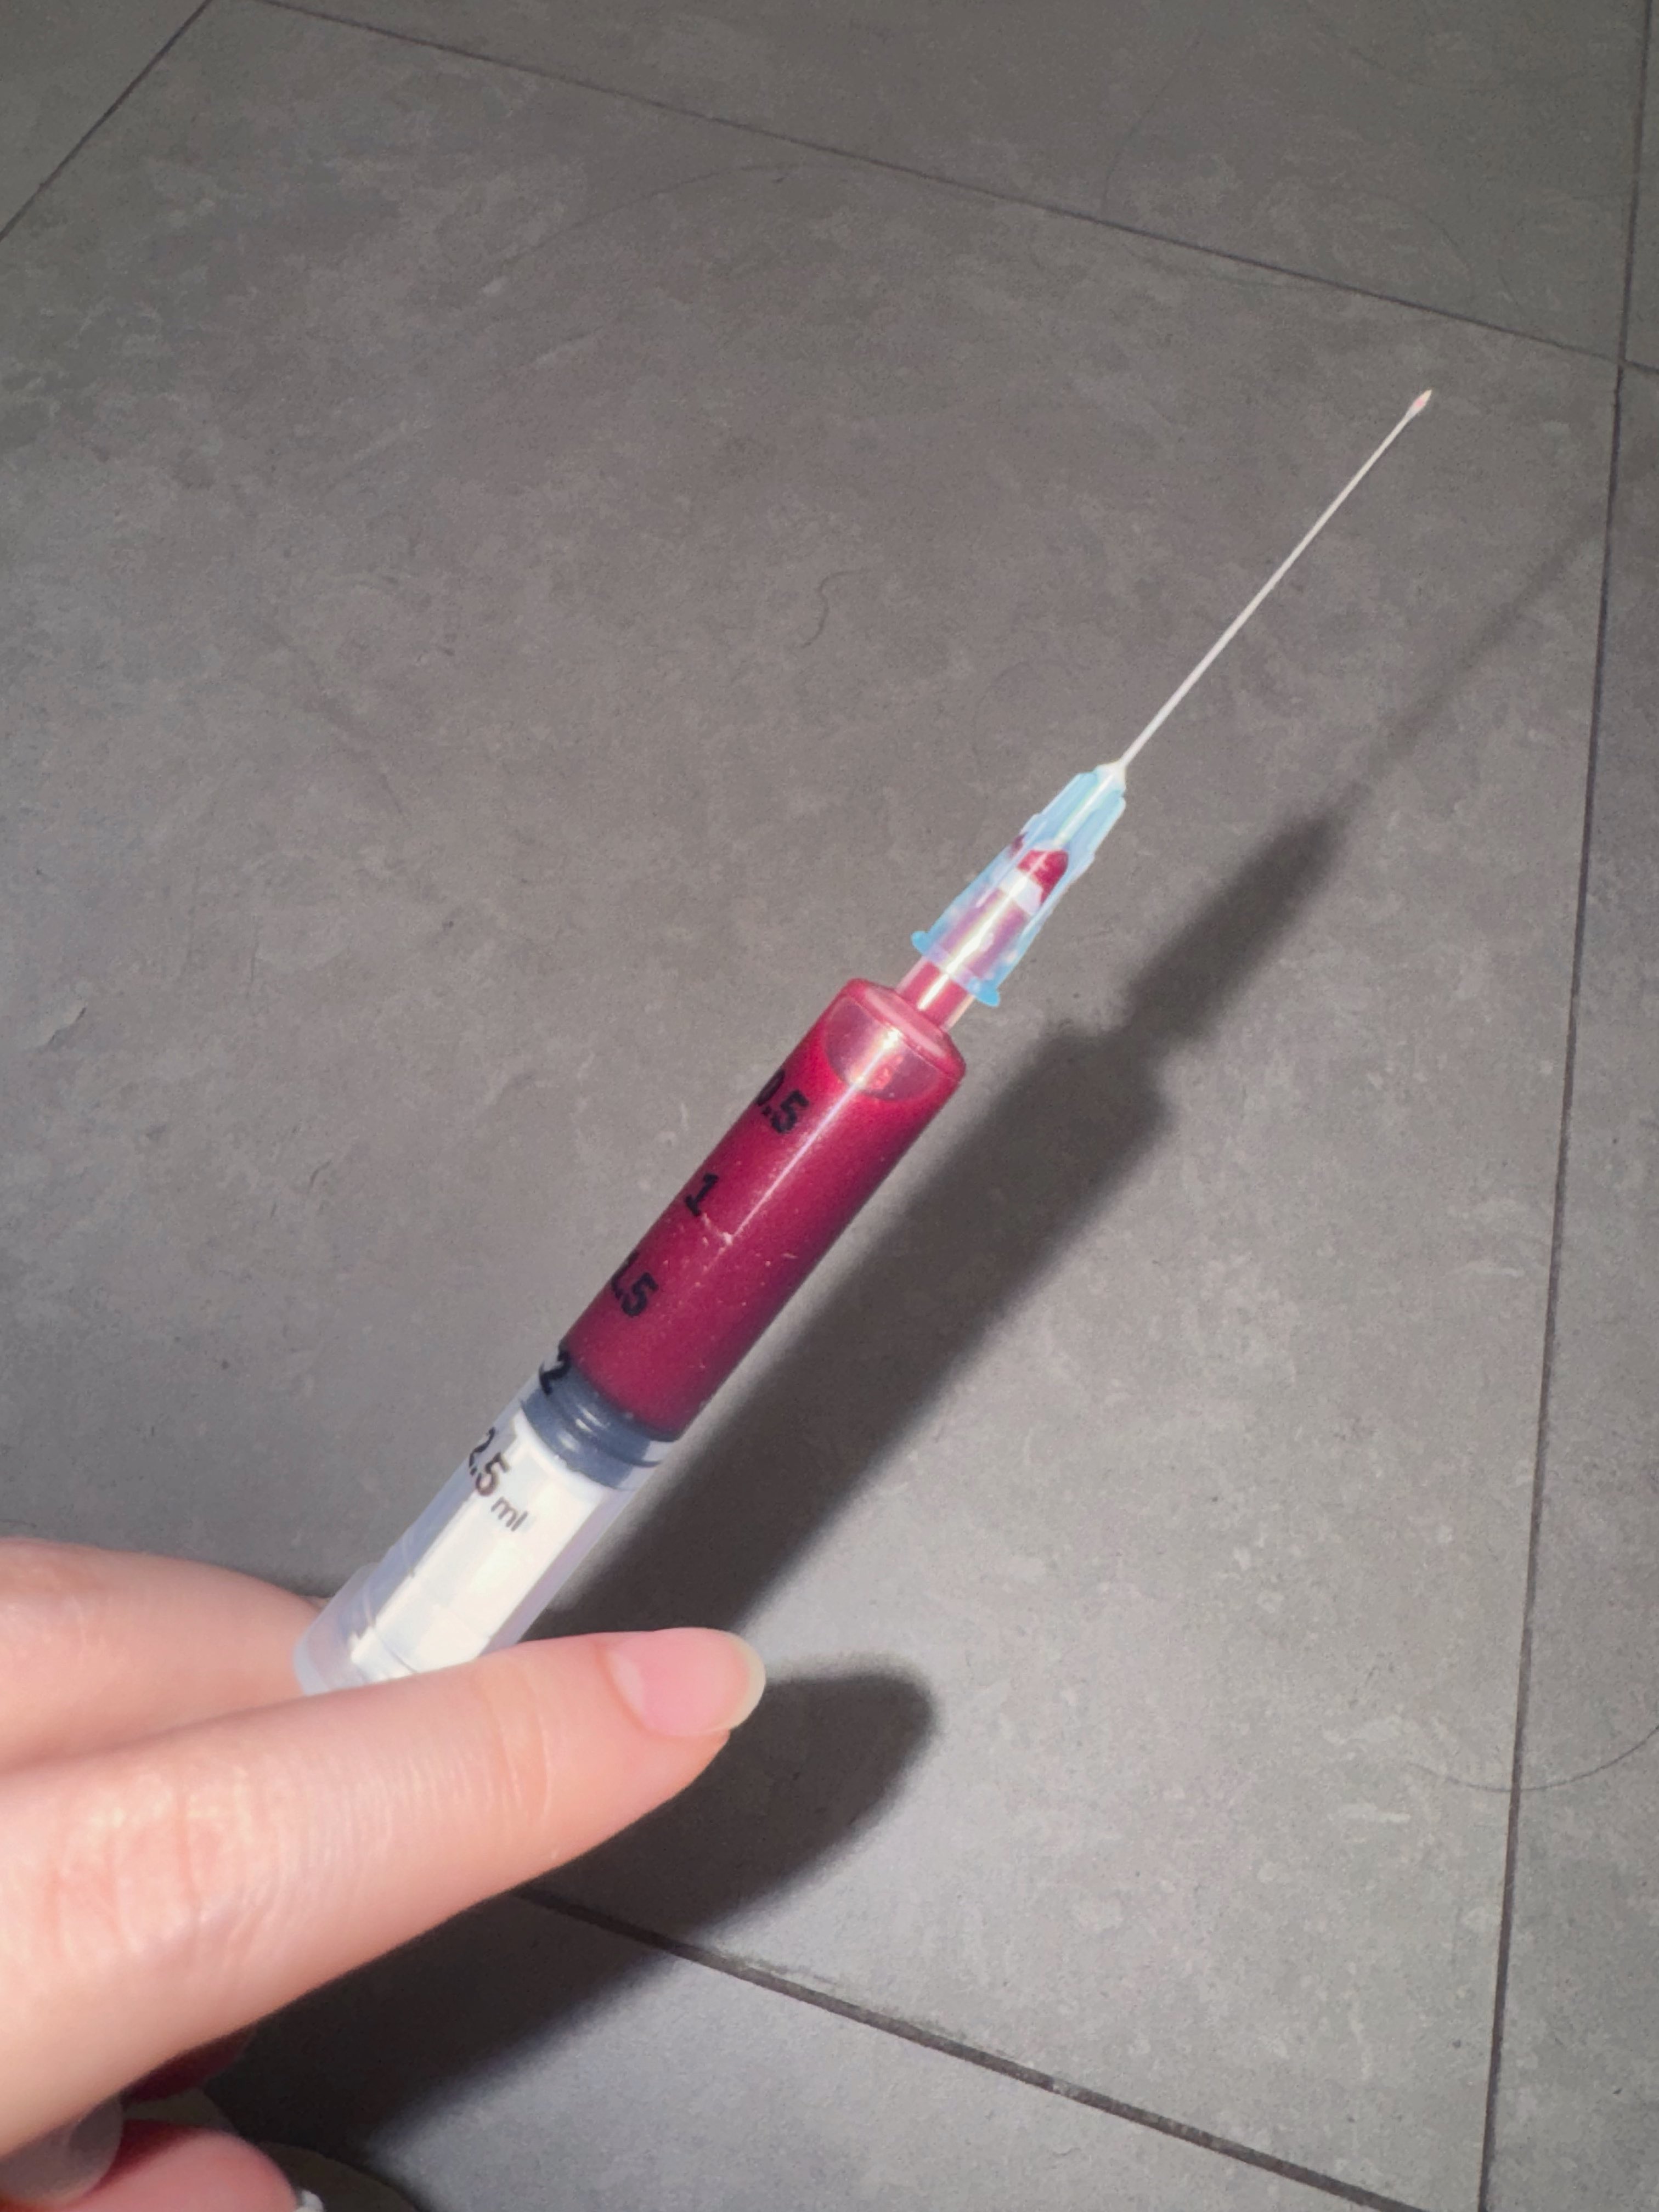

吃完唑吡坦会干一些难绷的事情,昨天睡不着疑似气急败坏了抽了0.5ml右美托咪定就是iv,还奇奇怪怪挑了个很痛的头静脉

后面不记得了,醒了灯开着的还以为是做梦,对着针孔一脸不可置信地整理记忆

你别说还扎得挺好的()按压时间估计也够,一点淤青也没有,不知道哪来的意志力 https://t.co/KxtfAUVSmb

2026-03-04 19:15:41 UTC

TEST FROPOFOL

果然蝴蝶针会翻车,太难用了。

最后用了留置针,推2ml.

本来是1ml,但忘记关闸血液回流,我怕把针管堵了于是又推了1ml

*我竟然无师自通留置针了!用的肘静脉因为其他地方被蝴蝶针霍霍了

提前推了利多卡因(也是测试倒抽)所以毫无痛感,耶

配合另一种麻醉就可以无痛重开了(bushi) https://t.co/Uj139Q2tBk

炽烈已极 @AnIncandescence竟然能在50mg下撑那么久,意志力比我想的还要强大,但是乱七八糟。

手上都是血迹不说,周围的其他地方也有我意料之外的血迹

p1床单和p2不知道怎么回事 应该是忘记止血了(?)毫无印象.jpg https://t.co/SknFUEwG2o[图片媒体不可用]

2026-03-04 23:02:13 UTC

炽烈已极 @AnIncandescence5ml好像也没那么强……撑着清理完之后已经不困了(。)